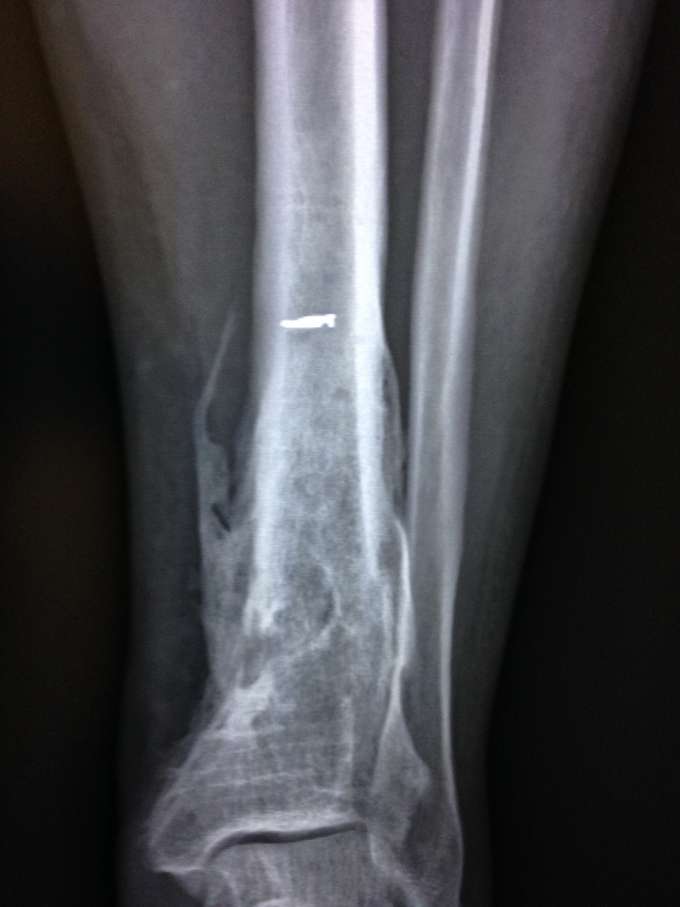

Ecco qualche foto:

Radiografie: si noti il buco nero che è il focolaio dell'infezione che ha mangiato l'osso (foto 1) e il callo osseo che si stacca a causa dell'osteomielite (foto 2)